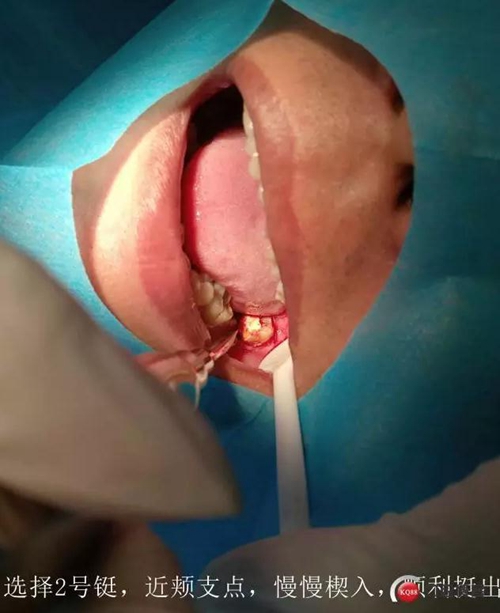

處置:38拔除

盡量囊腫刮除

如果強(qiáng)行一次完整取出,創(chuàng)傷會(huì)較大,神經(jīng)管損傷的可能性非常大,再者根尖區(qū)叩痛提示炎癥,不宜刺激

待頜骨骨壁恢復(fù)到離神經(jīng)管安全距離,再次手術(shù)比較安全。